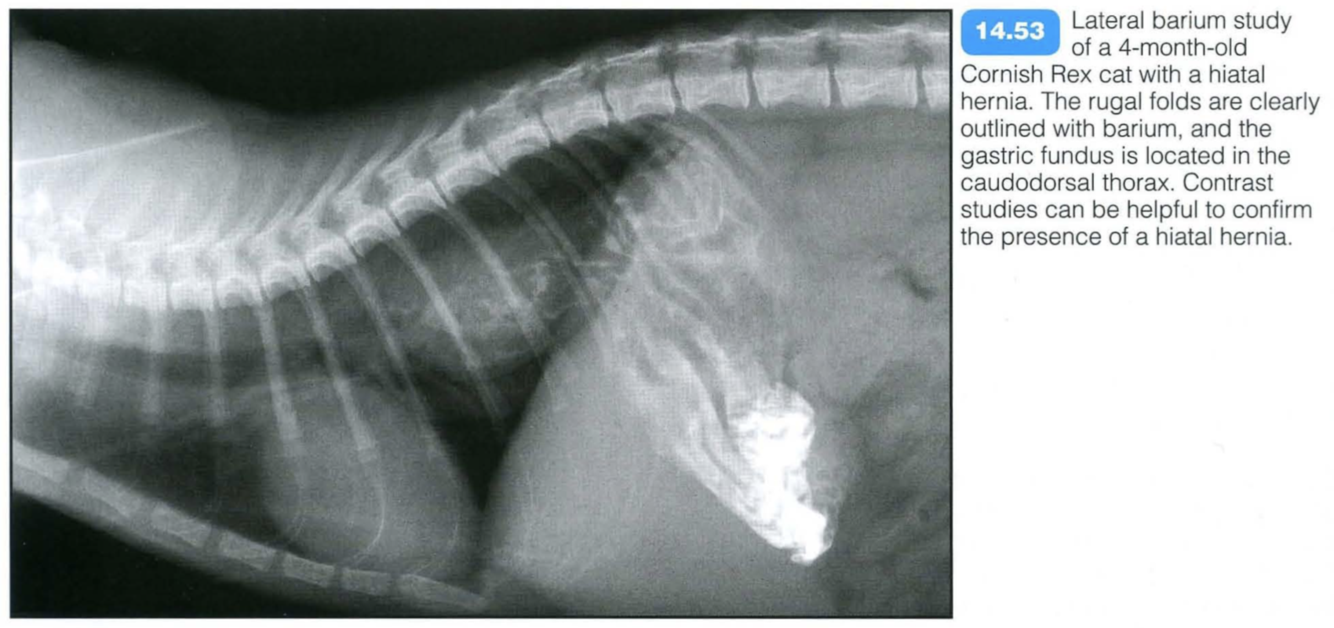

Sliding intramediastinal hiatal hernia:

The lower oesophageal sphincter moves freely back and forth into the caudal mediastinum, followed by parts of the stomach, through a loose oesophageal hiatus. Clinical signs include variable degrees of vomiting or regurgitation, hypersalivation and chronic weight loss. If the stomach is incarcerated, severe respiratory distress can be present. Aspiration pneumonia is frequently associated with this

Radiographic findings include:

Contrast studies may aid diagnosis: